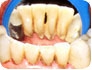

O tártaro é uma formação do depósito de placas bacterianas que reagem quimicamente com fosfato de cálcio da saliva, originando uma camada endurecida sobre os dentes. Deve ser removida pelo dentista e pode ser prevenido pela escovação e uso do fio dental.

A periodontite é a inflamação que atinge os tecidos periodontais, provocando a destruição desses, e do osso alveolar, responsável pela fixação do dente. Com sua evolução há o amolecimento do dente devido a perda óssea e ocasionando a perda do dente, (provocada pela presença do tártaro).

A placa bacteriana, com o tempo, poderá se mineralizar formando o tártaro ou cálculo gengival. Juntos, a placa e o tártaro deslocam as gengivas através da destruição das fibras que prendem o dente à gengiva. Se essa alteração não for tratada, a estrutura óssea que sustenta o dente poderá se comprometer e, a longo prazo, poderá ocorrer a perda do elemento dental. Esse abalo na estrutura óssea é denominado Periodontite (doença periodontal).